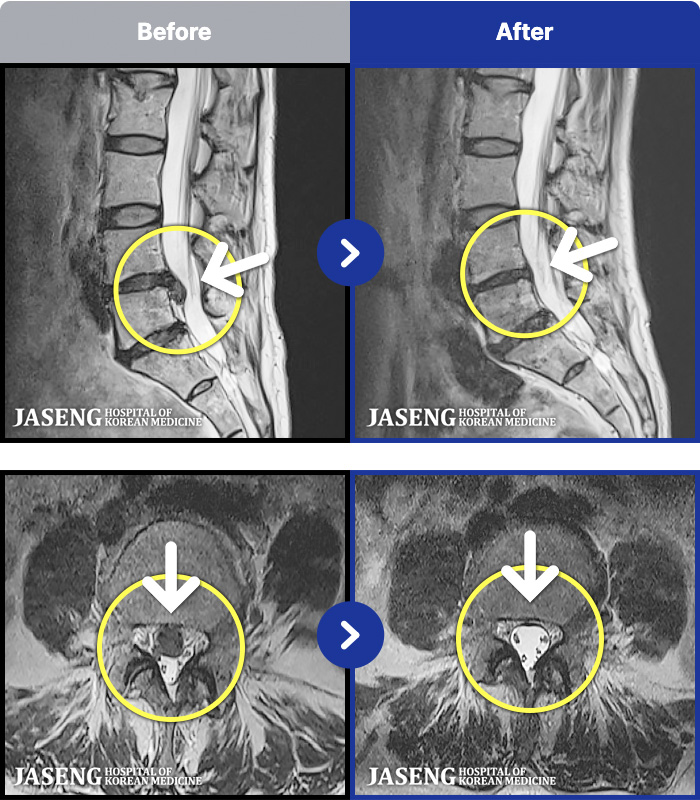

54 MRI ũ ʸ Ȯϼ.

ó ̾ ߰, ణ ٷϵ ݵǾ ϻȰ ¿ϴ. |